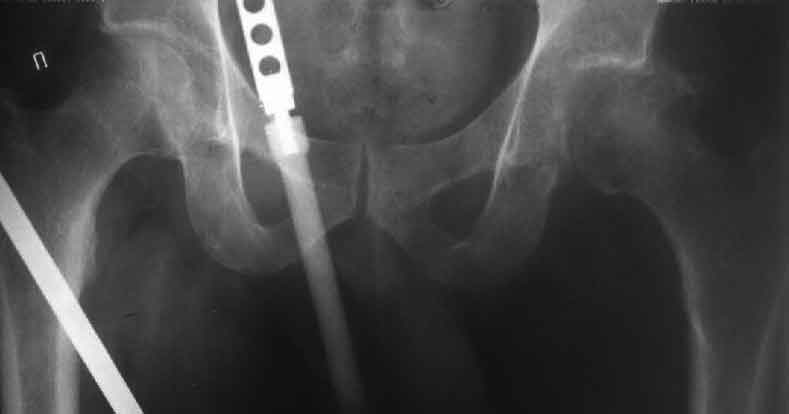

Коллеги, обещанный follow-up.

Больного прооперировали на прошлой неделе (цементный протез, цемент с гентамицином). Использовали задне-боковой доступ. В области перелома подвижности практически не было, так что тему сообщения уместно заменить на "неправильно сросшаяся шейка". И в головке, и во впадине

были значительные дегенеративные изменения, так что ни биполяр, ни остеосинтез тут неуместны (хотя это предлагали в ortopod'е). После релиза удлинили ногу на 3 см. Дальше удлинять побоялись из-за

натяжения седалищного нерва, хотя в принципе можно было бы еще 15-20 мм нарастить. По послеоперационной рентгенограмме анатомическое укорочение порядка 15 мм. Клинически при ходьбе - 4 см, но это за счет перекоса таза.

The patient underwent cemented THR on last week. Postero-lateral approach was used. There was only minimal motion at the fracture site and we had to cut the femoral head with oscillating saw. The femoral head was deformed with it's cartilage completely absent in some areas.

Acetabulum showed gross degenerative changes, especially in superior rim. So I think it was right choice not to do ORIF in this case. After some soft tissue release we've lengthened the leg up to 3 cm. Further lengthening was possible but we stopped at that moment due to tension of n. ischiadicus. Now patient walks with crutches. Leg length discrepancy is about 4 cm due to pelvic tilt (discrepancy on post-op x-ray is 15 mm).